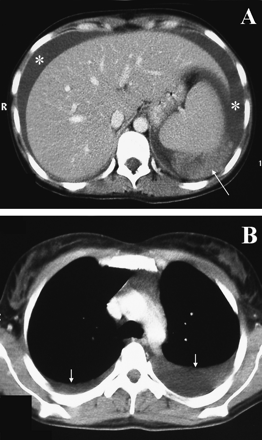

1. A 29-year-old woman in New Delhi, India was admitted with a 7-day history of fever, myalgia, and headache. She had had recurrent melena since the third day of illness. She was febrile and anicteric. No rash or lymphadenopathy was evident, and a tourniquet test was negative. Mild hepatomegaly and shifting abdominal dullness were present. Platelet count was 90,000/microliter; hematocrit was 33%. A peripheral blood smear did not show malarial parasites. Blood cultures were sterile. On hospital day 3, the patient had a sudden onset of abdominal pain and distension; hematocrit dropped to 15%. Abdominal computed tomography is shown in the Figure. Paracentesis yielded frankly hemorrhagic fluid with a hematocrit of 11%.

What caused this precipitous decline? What is the underlying infectious process?